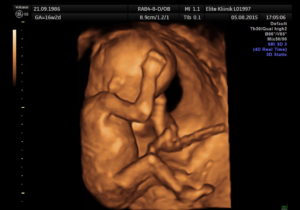

Многие будущие мамы предпочитают пройти 3д-сканирование – его принцип основан на таком же способе, как и обычное УЗИ, однако трехмерное изображение позволяет выявить пороки сердца и аномалии развития центральной нервной системы. Качественный снимок УЗИ в 14 недель позволяет разглядеть пропорциональное тело крохи, намечающийся волосяной покров на головке, брови и реснички, заметить выражение личика крохи и сходство с родителями.

Но отличаться 3д картинка от 2д будет существенно. На рисунке показаны примеры в двух режимах ультразвукового сканирования.

Рисунок 2. 3д

хорошо определяются структуры лица

Как видно на приведенных выше примерах, изображение при двухмерном сканировании плоское, а разобрать детали на нем может только опытный профессионал. При трехмерном картинка больше напоминает своеобразное «фото» малыша.

Рисунок. 3д

картина в первом триместре